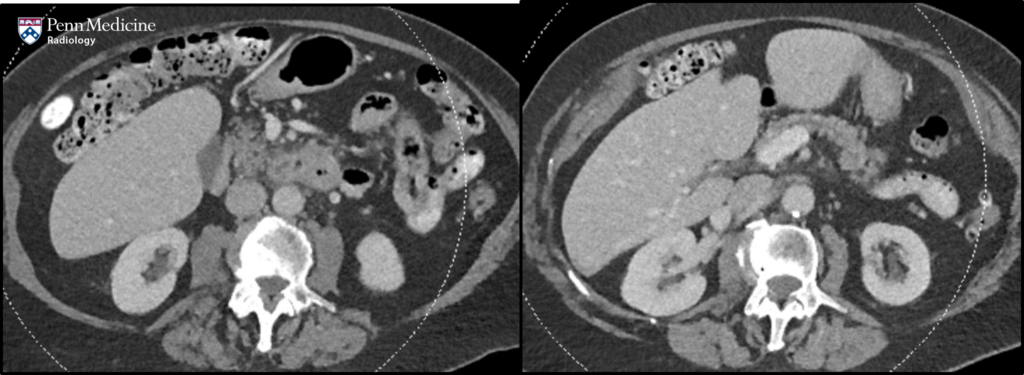

32-year-old man with incidental liver lesion

A 32-year-old man presented for further evaluation of an incidental liver lesion.